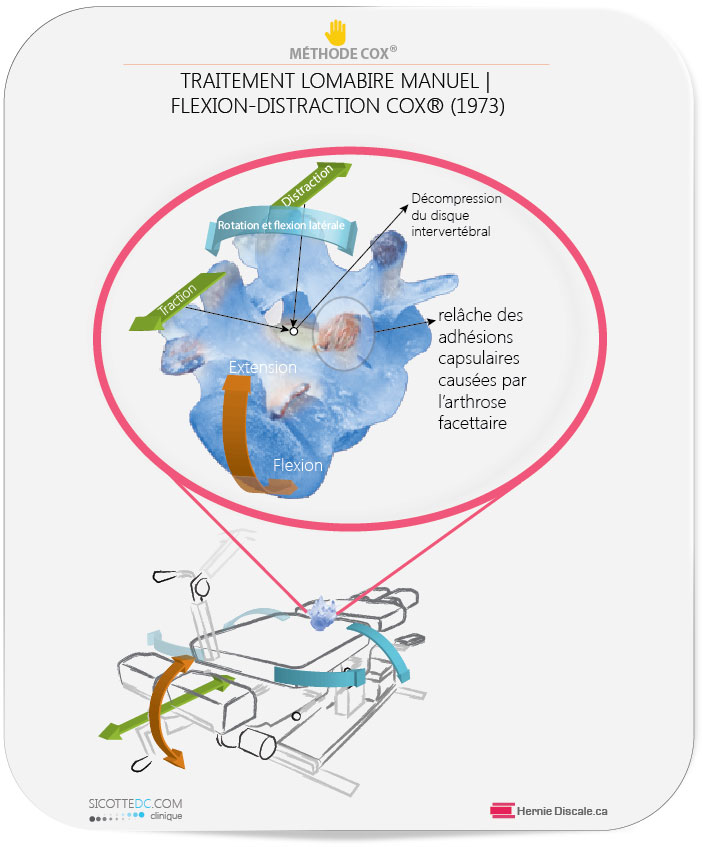

COMMENT LE TRAITEMENT NATUREL COX® AIDE À DIMINUER LES EFFETS NÉFASTES DE L’ARTHROSE LOMBAIRE

L’objectif est de mobiliser les segments où se trouve la discarthrose (discopathie) vertébrale.

COMMENT FONCTIONNE UN TRAITEMENT COX®